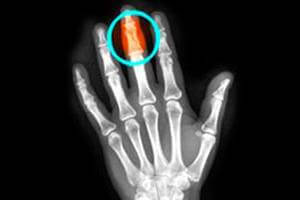

Лечащий врач может назначить несколько физиотерапевтических процедур, направленных на восстановление травмированного пальца. При соблюдении всех условий лечения, от ушиба не останется и следа, для собственного успокоения можно сделать в поликлинике рентгеновский снимок (фото ушибленного пальца).